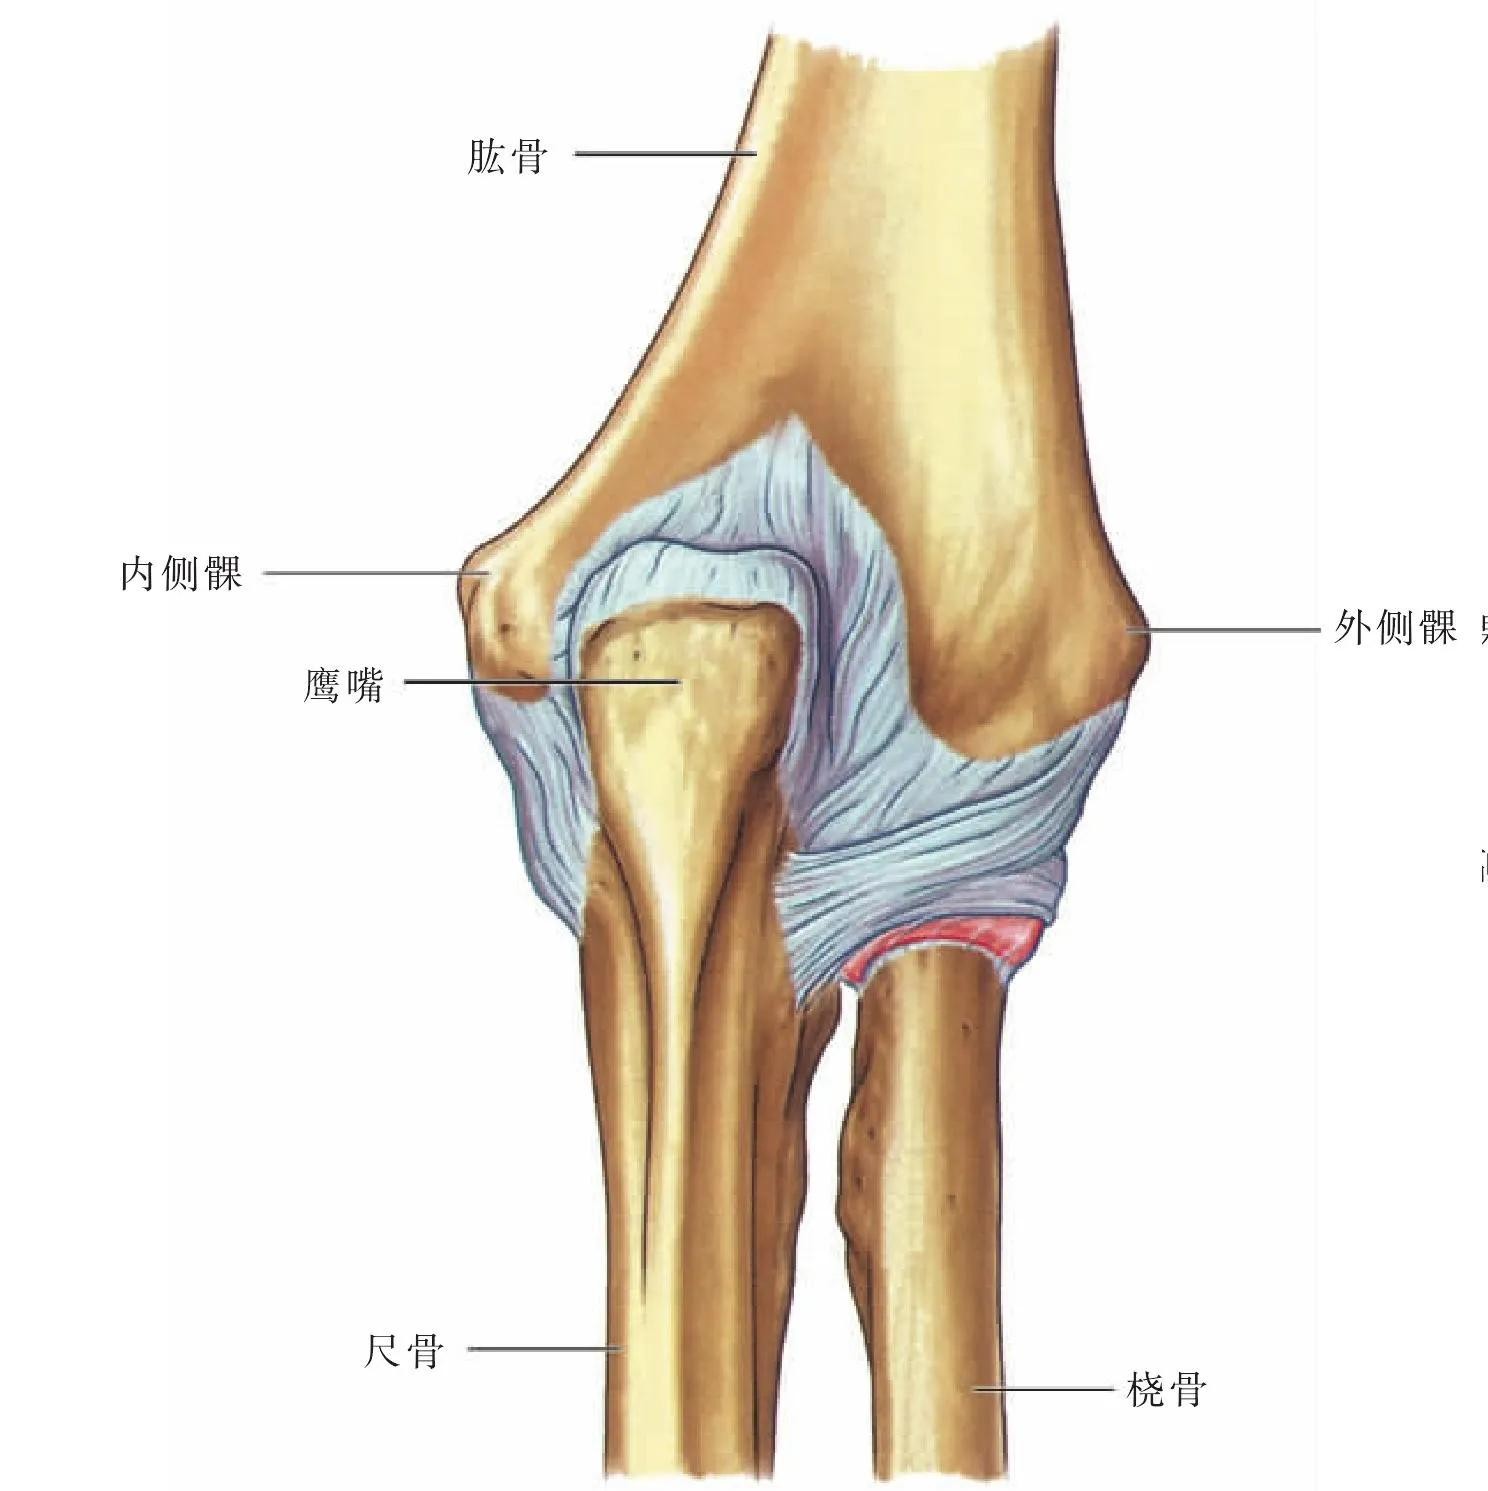

肘关节属于复合关节。是由肱骨、桡骨、尺骨和肘部的关节囊,还有周围的韧带组成的。肘关节包括了肱尺关节、肱桡关节和上尺桡关节三个关节。

肘关节正位图片上大致可以看到肱骨、尺骨、桡骨、尺骨鹰嘴、内上髁、外上髁及桡骨小头。